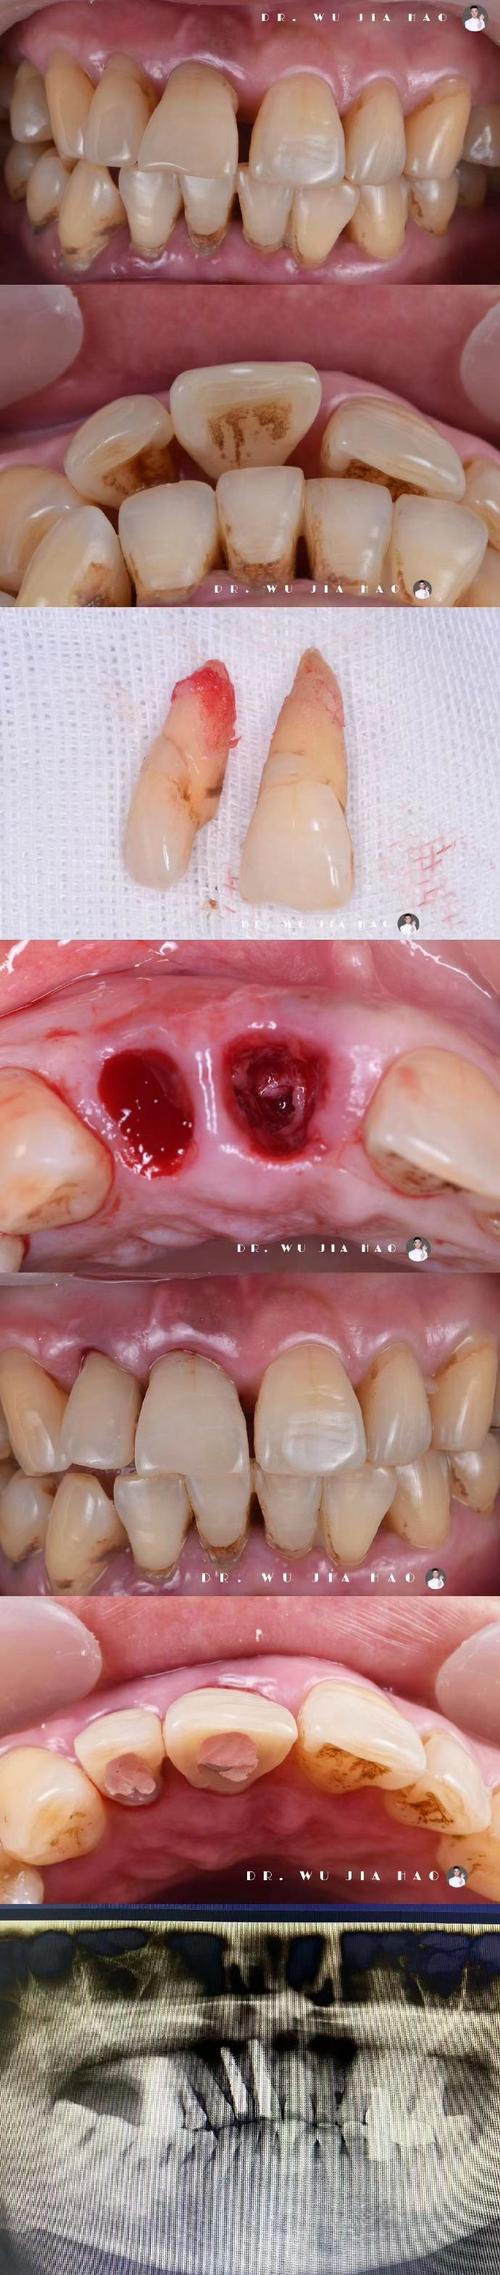

种牙植骨手术需在牙槽骨内制备种植窝、植入骨粉,这一过程可能损伤周围小血管,导致术后短期内少量渗血,属于正常现象,但若出血量较大或持续时间较长,可能与以下因素有关:

- 手术创伤:术中操作可能损伤牙龈黏膜、骨膜或小动脉,尤其骨粉植入后局部血供丰富,若缝合不严密或压迫不足,易引发出血。

- 局部感染:术后若口腔卫生维护不佳,细菌滋生引发创口感染,可能导致组织坏死、血管破裂,出现渗血或脓血性分泌物。

术后少量渗血(唾液中带血丝、24小时内出血量<5ml)通常无需特殊处理,可通过局部压迫、调整护理习惯缓解;若出血量较大(如血凝块持续脱落、出血超过30ml/小时)或伴随头晕、心慌等不适,需立即采取措施:

- 及时就医:若压迫后出血仍无法控制,或出现活动性出血(血液持续涌出),需返回医院就诊,医生可能通过缝合、电凝或填塞止血材料等方式处理。